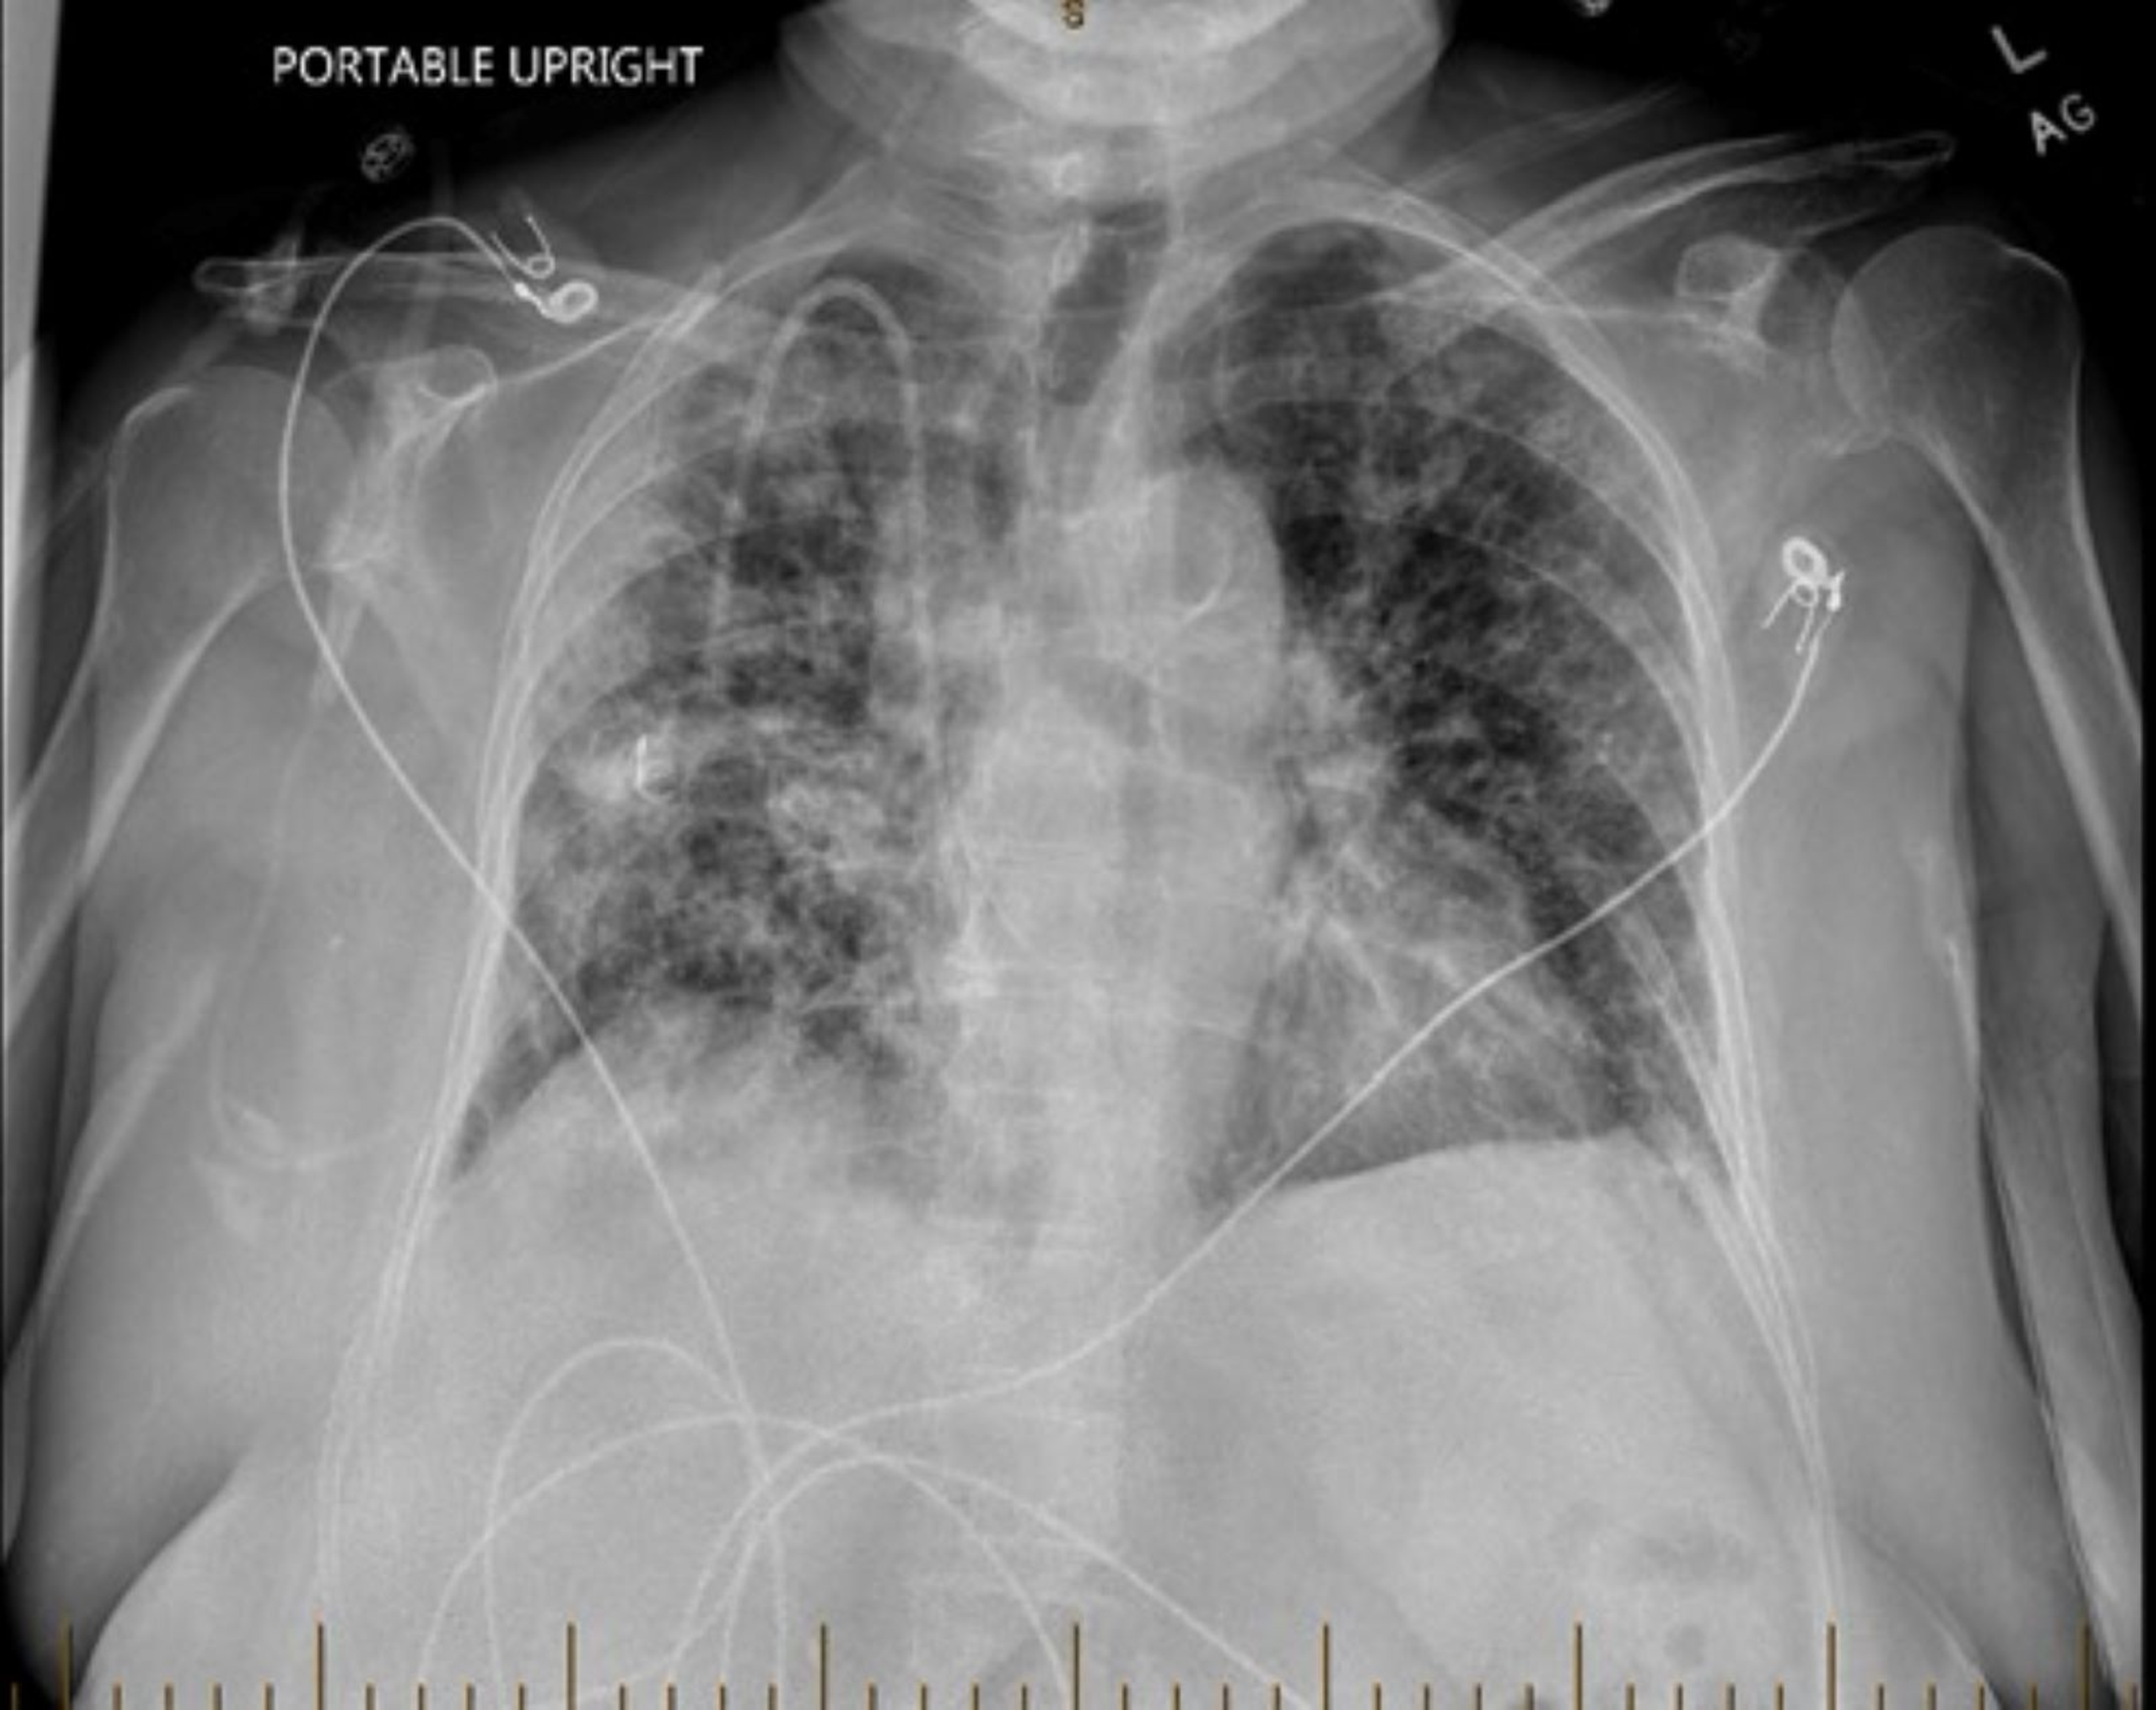

Bleomycin lung toxicity pneumonia pattern) Image Bleomycin Lung Toxicity Oxygen bleomycin is an antineoplastic agent with potential for producing pulmonary toxicity, attributed in part to its free radical. bleomycin is a cytotoxic agent that is used in multiple malignant diseases, including hodgkin lymphoma and can. Risk factors such as age and g. exposure to bleomycin appears to sensitise the lungs and potentially fatal acute lung damage can. Bleomycin Lung Toxicity Oxygen.